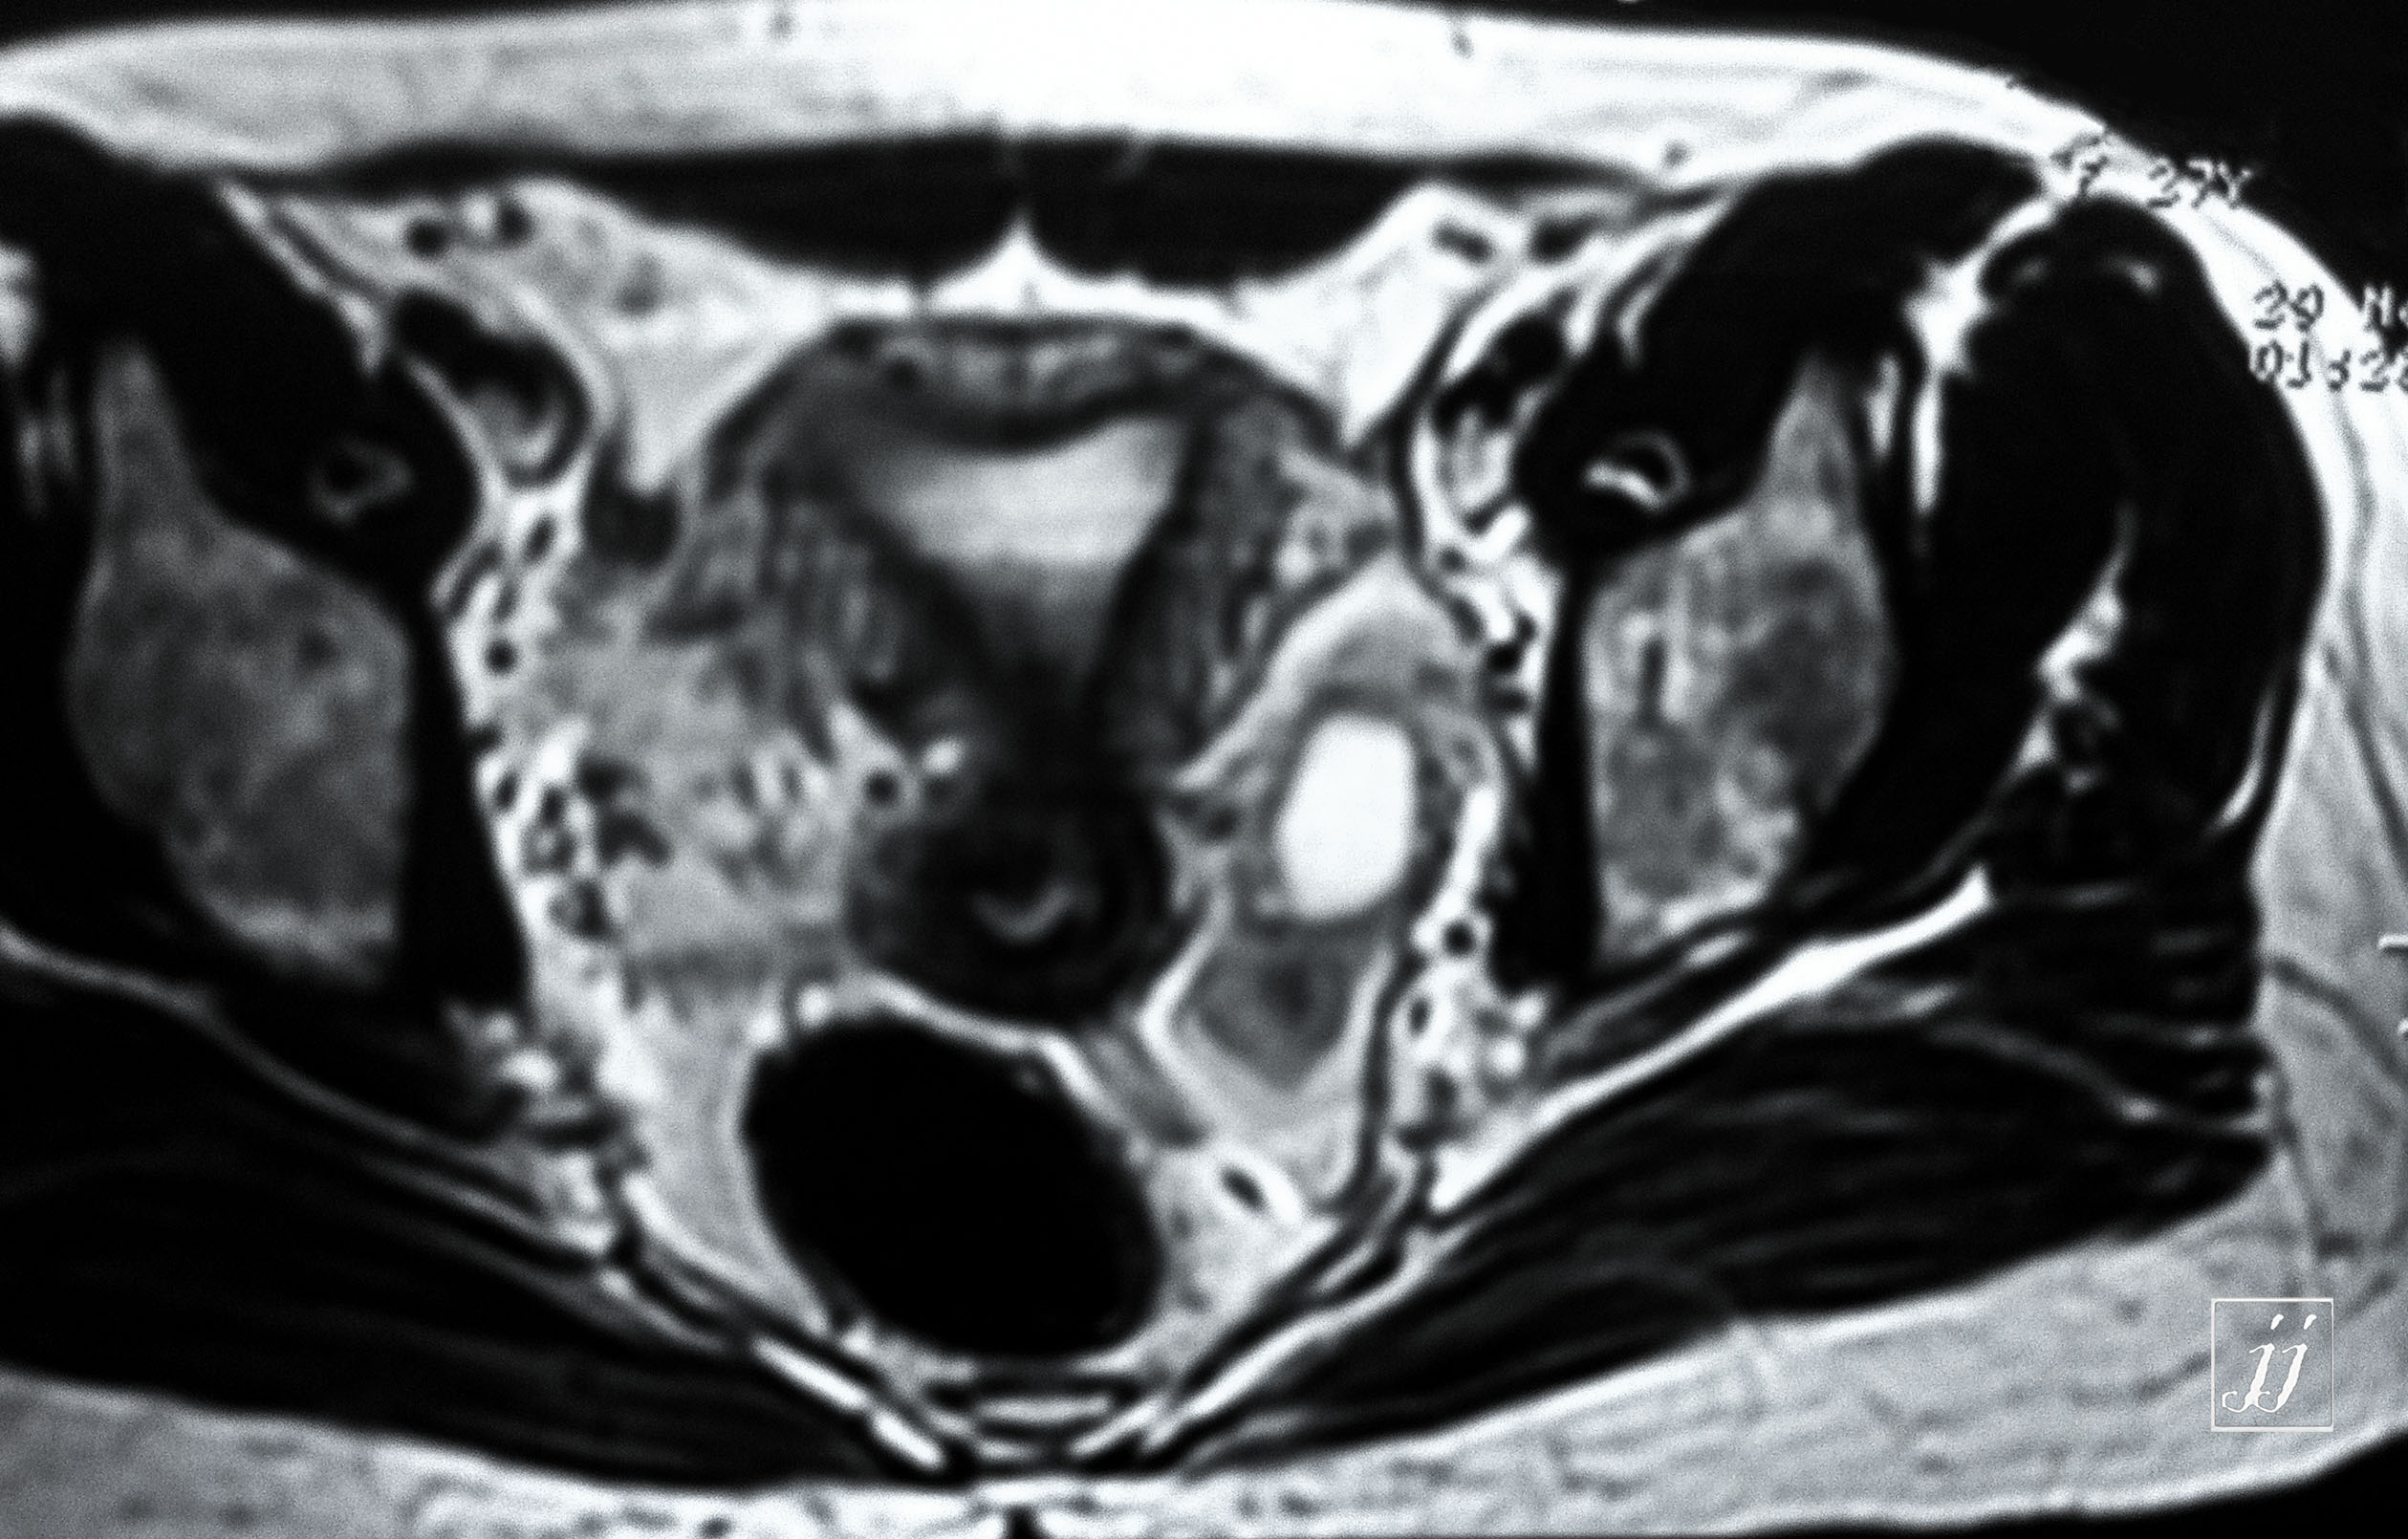

Abdomen- left side endometriosis vs dermoid cyst (9)